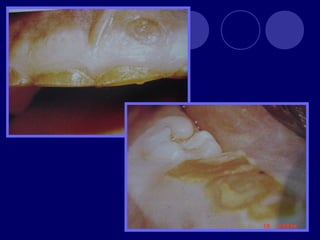

DENTINOGENESIS IMPERFECTA TIPO I:asociada a padecimiento esquelético, asociada a osteogénesis imperfecta (escleróticas azules, sordera, múltiples fracturas,etc.)  Dos denticiones  Dientes blandos, consistencia terrosa  Rx: cámaras pulpares obliteradas

TIPO II:  Dientesde color: amarillo, pardo azulado u opalescente con brillo translúcido, raíces color ámbar  Rx: coronas bulbosas, cámaras pequeñas o ausentes, raíces delgadas y cortas TIPO III: (SHIELDS)  Temporal: translúcido, ámbar  Permanente: normal

DISPLASIA DE DENTINA TIPOI DE SHIELDS O DISPLASIA DENTINARIA RADICULAR:  Raíces cortas  Temporal: cámaras pulpares obliteradas  Conductos radiculares no se distinguen TIPO II DE SHIELDS O DISPLASIA DENTINARIA CORONAL :  Pulpolitos

OSTEOGENESIS IMPERFECTA Alteración deesmalte y dentina En la dentición temporal no hay esmalte y dentina muy abrasionada En la dentición permanente esmalte frágil color grisáceo y amplias zonas desprovistas de éste, dentina atípica

ODONTODISPLASIA REGIONAL  Dientefantasma  Dientes en forma de concha, pequeños con escasa raíz, amplias cámaras pulpares  Rx: aspecto fantasmagórico

HIPOFOSFATASIA Incapacidad de lososteoblastos de formar fosfatasa alcalina Movilidad dental Rx. Cámaras pulpares y conductos radiculares amplios.